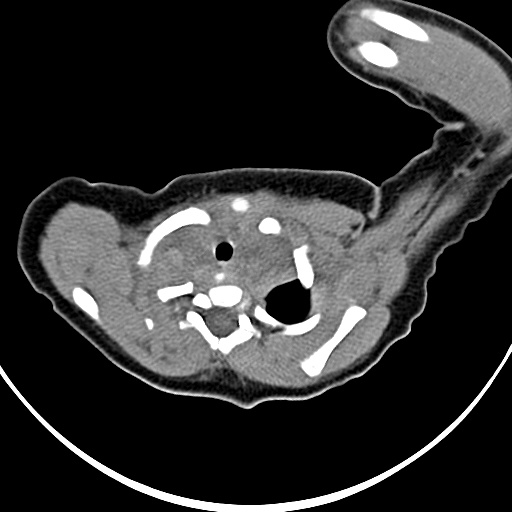

标题: PED1779:左侧锁骨下方异常密度影 请指教 [打印本页]

标题: PED1779:左侧锁骨下方异常密度影 请指教

患者,男,1月,出生后一月,无明显诱因出现颈部左前方肿块。体检:左侧颈部轻度凸起包块,触之较硬。

病灶与左侧胸锁乳突肌分界不清,软组织密度,不似囊性改变,从病人的年龄及病变性状首先要除外先天性斜颈(肌性斜颈)可能。

作者: 祥云 时间: 2009-3-7 04:30

左侧胸锁乳突肌肿大,考虑产伤所致

胸锁乳突肌挛缩(斜颈)?